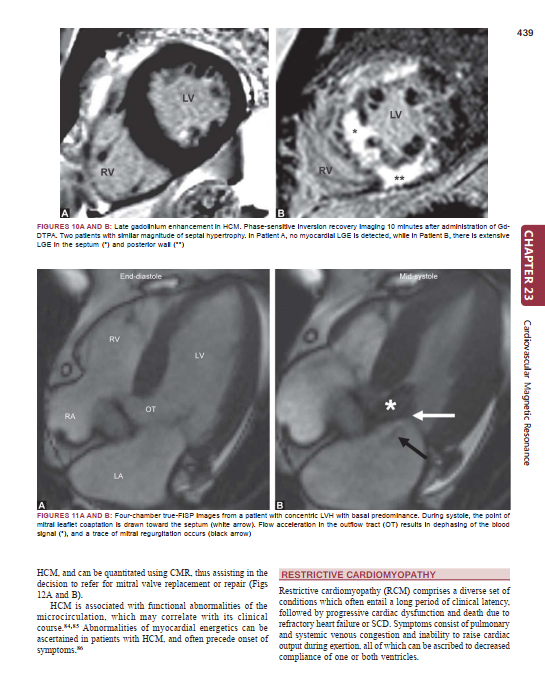

Description